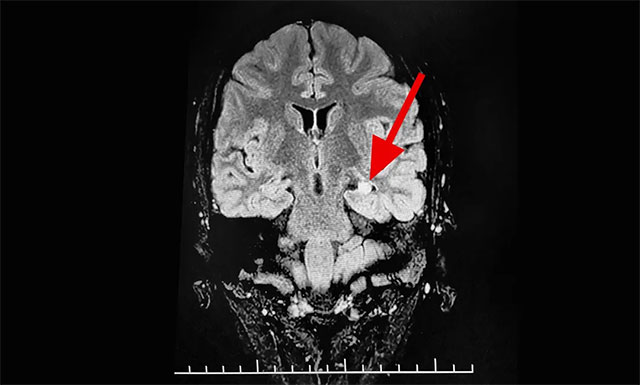

▲ 通过系列检查最终明确患者致癫灶

来到该院后,医院脑电监测崔丽华主任应用先进的美国尼高力长视频脑电图仪为玲玲做了24小时脑电监测。崔丽华主任根据脑电图监测分析指出,患者玲玲颞区有癫痫波,左侧较为严重。磁共振检查后发现,患者颞叶、海马结构异常。